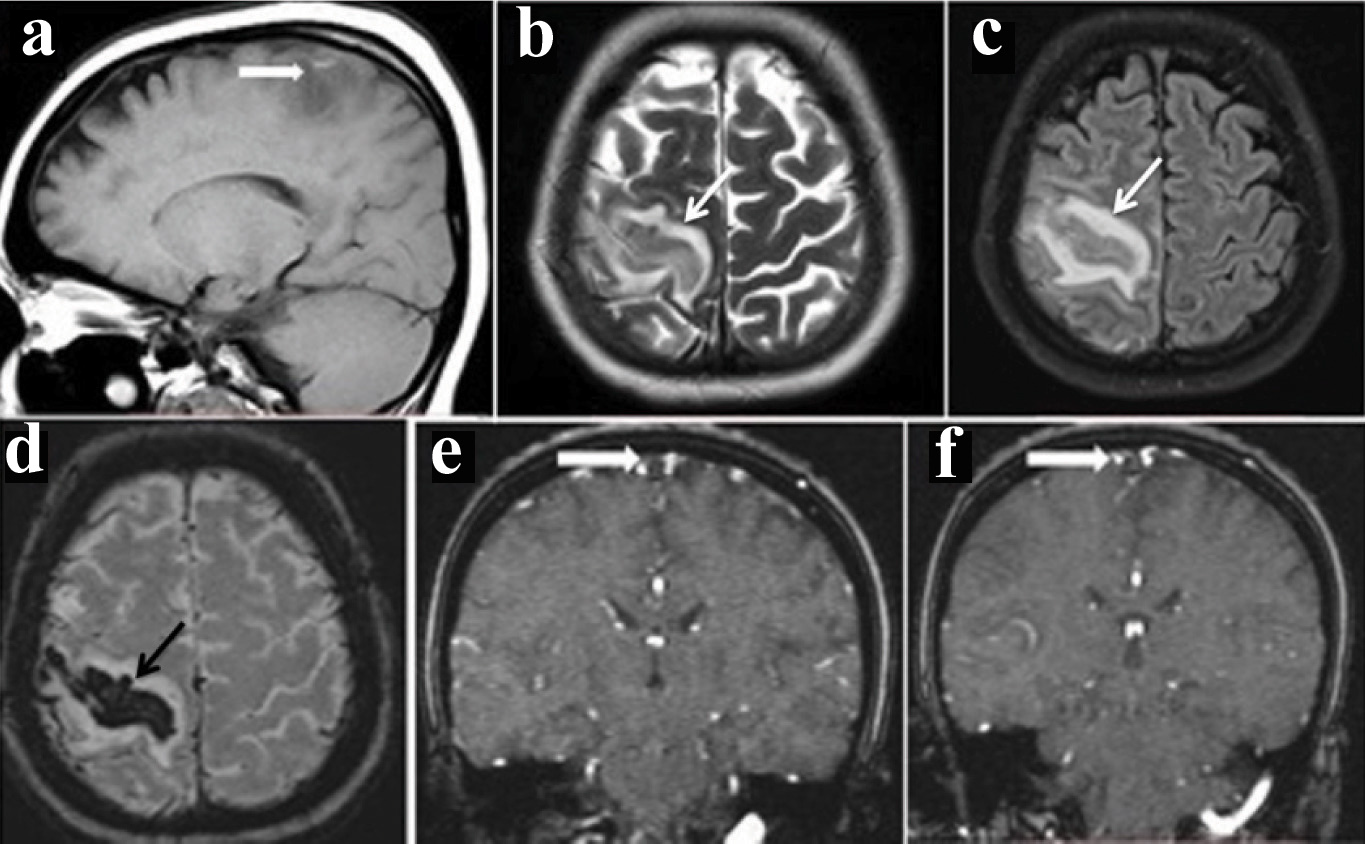

Magnetic Resonance Imaging (MRI) revealed altered signal intensity in the region of right perirolandic gyrus with surrounding oedema [Table/Fig-1a-c], corresponding blooming on Susceptibility weighted Imaging (SWI) [Table/Fig-1d], 2D TOF MR venogram demonstrated absence of flow in superior sagittal sinus [Table/ Fig-1e&f].

Table/Fig-1a-f]: (a)- Sagittal T1 image show hyperintensity with adjacent oedema; (b&c)- correspondingaxial regions in T2 and FLAIR show hypointensity and adjacent oedema; d- Axial susceptibility weighted(SWI) show blooming suggestive of haemorrhage; (e&f)- Coronal time of flight (TOF) venogram show absence of flow in the superior sagittal sinus (empty delta sign) indicating thrombosis.